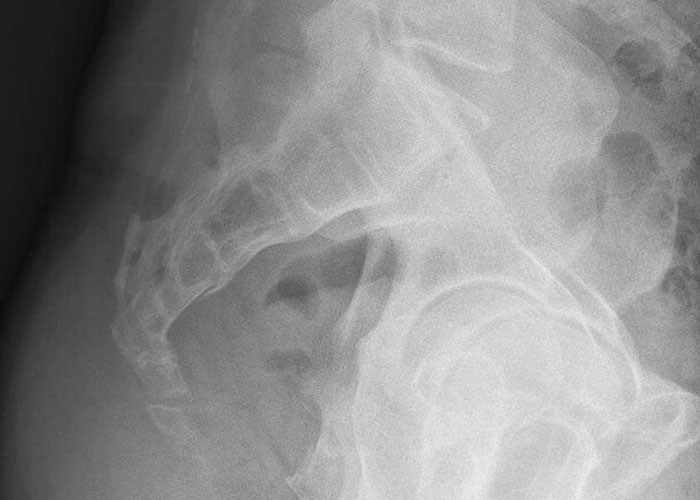

#32

My grandpa’s heart was in his body backwards, discovered when he had a heart attack and needed surgery. All his other organs were oriented correctly, just his heart was backwards.